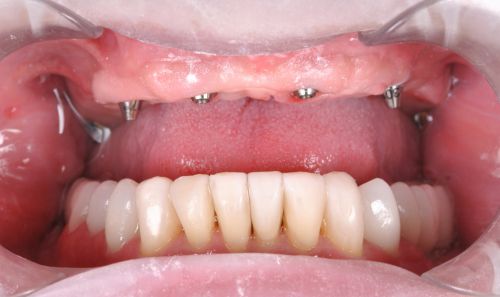

Wykonana praca protetyczna:

- most pełnołukowy na sześciu implantach

- korony na zęby własne w łuku dolnym

- korony na implantach w miejscach braków zębów

- odbudowa flow-injection zębów dolnych przednich